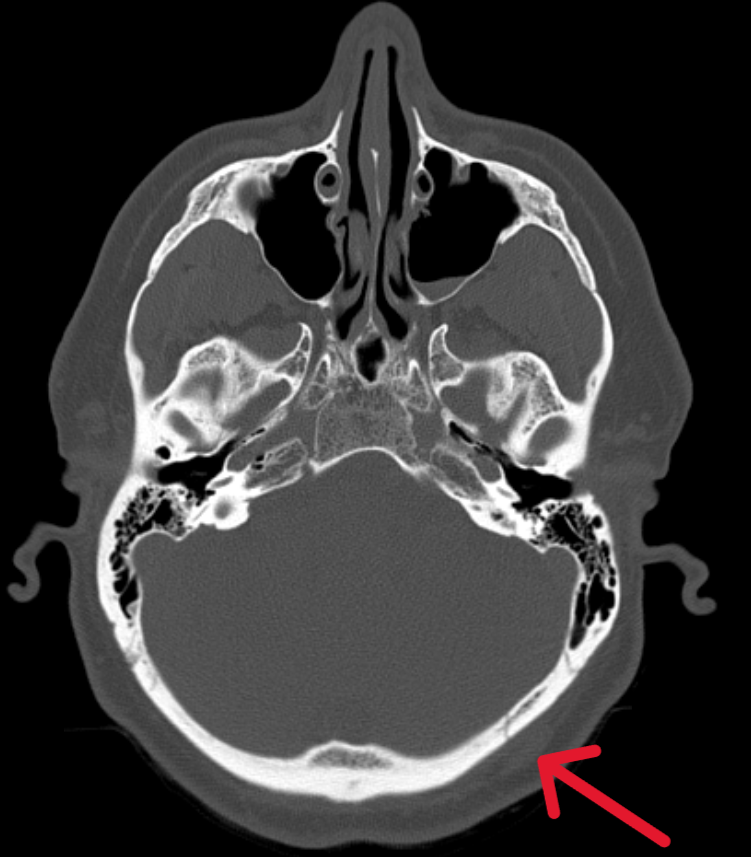

Пациент обратился в Ильинскую больницу, где была проведена компьютерная томография головного мозга и выявлены следующие изменения:

• перелом затылочной кости слева (то место, куда пришелся удар при падении);

• ушиб (контузия) мозга с геморрагическими включениями в правой лобной доле (противоположная от удара сторона).

Такой механизм травмы обусловлен тем, что мозг имеет подвижность внутри черепной коробки и после первого удара «отскакивает» и ударяется о противоположную стенку черепа.